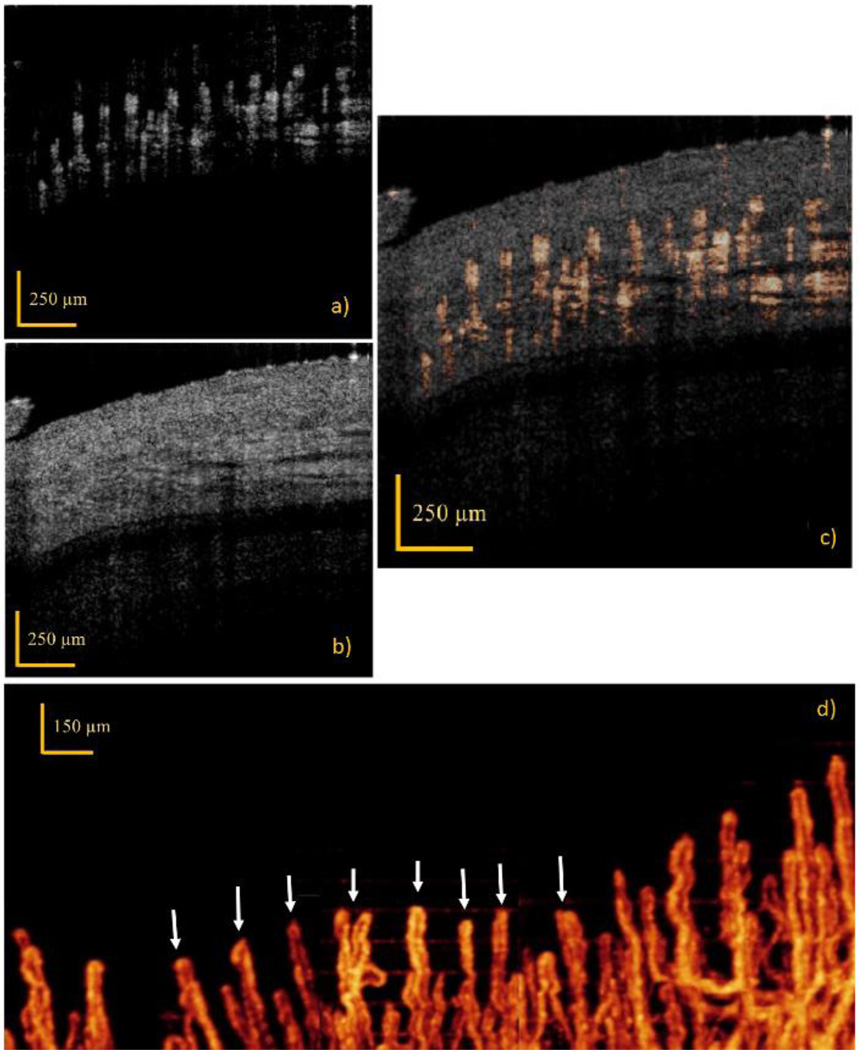

The volumetric UHS-OMAG imaging results of capillary network in the vicinity of the previously imaged area (Fig 1(b–c)) is given in Fig. 2. The maximum intensity projection view of capillary loop region at 150 – 400µm depth is demonstrated in Fig 2(d), which is arranged to stay in the depth of focus of the lens. Three images captured at adjacent regions are combined to extend the visualized area. The corresponding capillaries shown in the bidirectional flow image (Fig. 1(b–c)) is pointed out in Fig. 2(d) with white arrows. By combining Fig. 2(d) with Fig. 1(b), the size, the shape and the orientation of the arteriole-end and venule-end capillaries can be extracted along with RBC velocity information.

Figure 2.

In vivo imaging results obtained by UHS-OMAG. (a–c) Cross-sectional images along the B-frame, where (a) shows the flow image, (b) show the structural image, and (c) show the flow image stitched on top of the structural image. (d) UHS-OMAG maximum intensity projection view of microcirculation network at 150 – 400µm depth, where 3D vascular signals are projected into a single image. White arrows point out the corresponding capillary loops where RBC velocity is mapped in Fig 1(b). Comparing this figure with Fig. 1(b–c), the arteriole-end capillary can be differentiated from venule-end capillary.